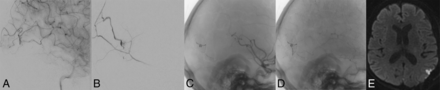

Arterial emboli following endovascular and surgical treatments of DAVFs in 2 patients. Two middle-aged male patients undergoing posttreatment angiography were identified as having middle cerebral artery emboli (A and C, white arrows). Both patients were heparinized, and the second patient underwent superselective intra-arterial tPA treatment with minimal clot lysis. Postangiographic DWIs (B and D) demonstrate small cortical infarctions in territories associated with the MCA emboli. Although the first patient's MCA thrombus (A and B) is adjacent to the original DAVF, the second patient's is not (C and D).